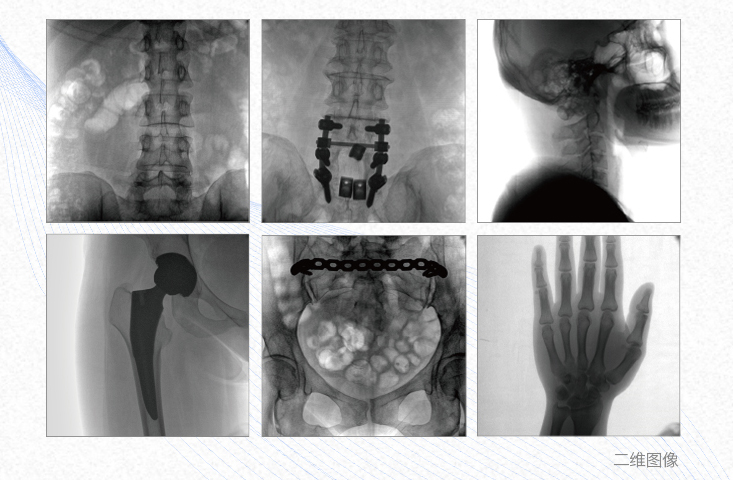

1、脊柱外科

有效重建復雜的脊柱三維模型,提供準確的二維、三維圖像,提高螺釘植入的準確性,縮短手術時間,減少并發癥的概率,降低輻射的攝入。

2、創傷外科

例如骨盆骨折內固定術,可術中三維重建髖臼關節面,準確定位并植入螺釘,有效縮短螺釘植入的時間和透視暴露時間,減少術中及術后并發癥發生的概率。

3、關節外科

主要應用于肩關節、肘關節、髖關節、膝關節的關節置換及解剖復位的定位。它可以準確地置入假體,減少輻射時間,降低輻射劑量。

4、截骨矯形外科

例如治療先天性脊柱側后凸畸形,可有效引導術者植入后路螺釘并切除半錐體,達到滿意的截骨矯正效果。